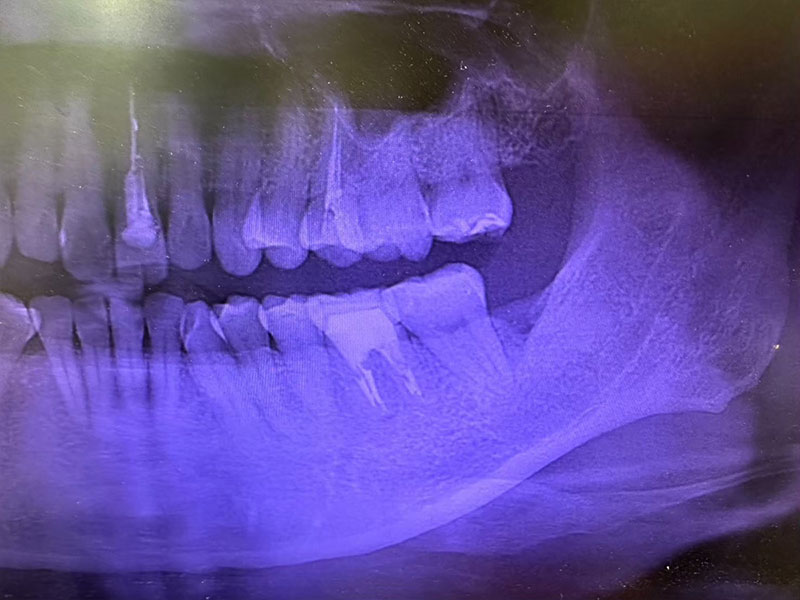

治療前

治療後

女性 30歳

治療期間 1週間

回数 2回

費用 保険適用

親知らずが横向きに生えていたり歯ぐきの中に隠れている場合、歯磨きが行き届かず汚れがたまり、腫れて痛くなったり虫歯や歯周病の原因となったりします。隣の歯にも悪い影響があり口臭の原因ともなるため早めに抜歯した方がよいことが多いのです。